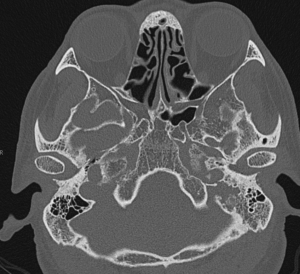

1、胸部X線片表現 與其他神經源性腫瘤相似的X線徵象,後縱隔椎旁溝有大小不等的腫塊陰影,亦有顯示腫物在升主動脈後上方,與脊柱重疊,密度均勻,邊界清晰。當腫瘤與主動脈瘤、頭臂動脈瘤無法鑑別時採用選擇性的動脈造影,可明確顯示出血管的來源。30%的病例在胸部動脈造影中能見到腫瘤毛刺,對術前腫瘤的診斷定位有一定幫助。